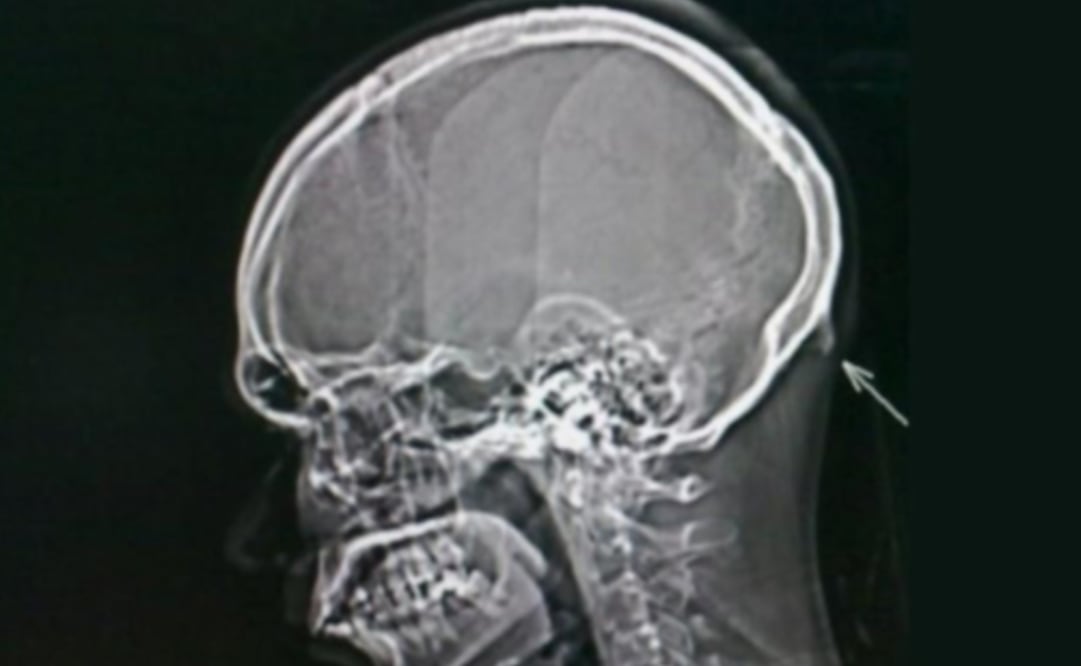

Llamado protuberancia occipital externa ; este “ cuerno ” aparece en la parte posterior de la cabeza , por encima del cuello y, de acuerdo con el doctor Shahar , puede sentirse al tacto , e incluso llega a ser visible en personas calvas.

El investigador descubrió el “ cuerno ” al revisar a 218 personas de entre 18 y 20 años de edad, en el año 2016. Un 41% de los sujetos muestra revelaron el pequeño pico de más de 10 milímetros, así lo indicó en una entrevista para el medio británico BBC.